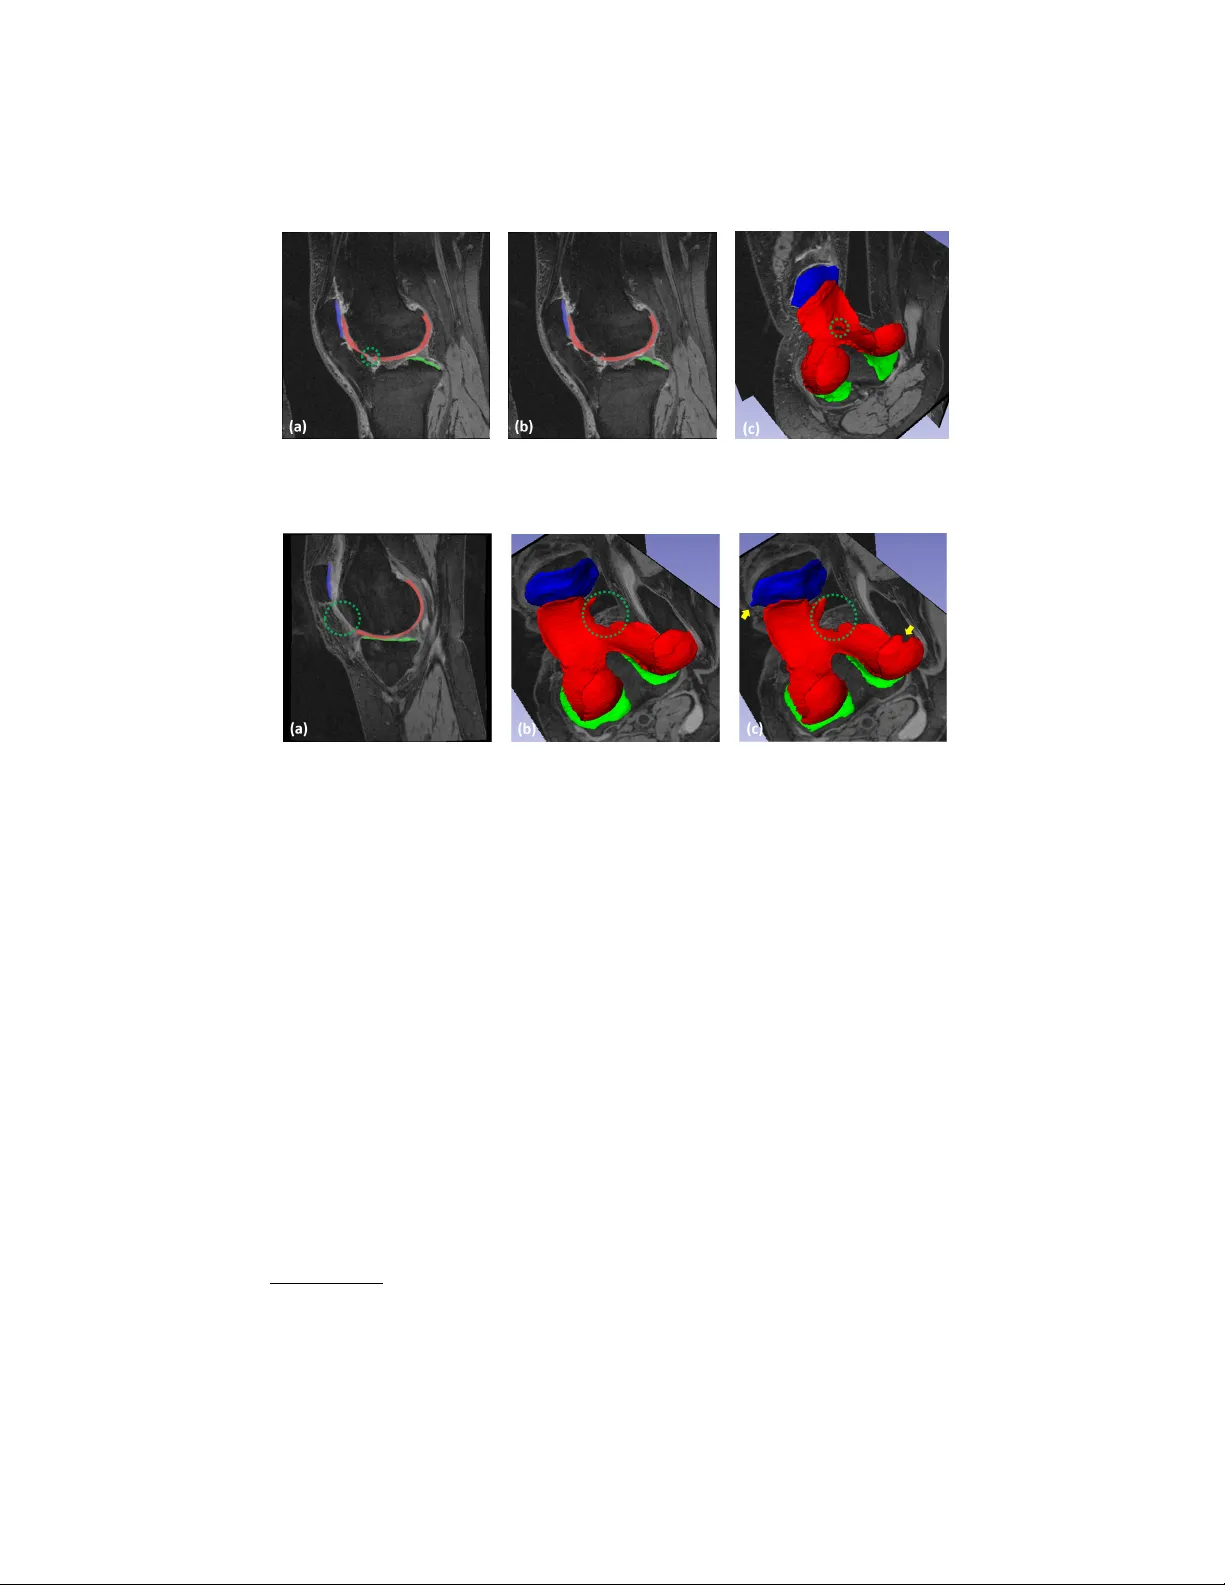

Collab orativ e Multi-agen t Learning for MR Knee Articular Cartilage Segmen tation Chao wei T an 1 , Zhennan Y an 2 , Shaoting Zhang 2 , Kang Li 1 , 3 , and Dimitris N. Metaxas 1 1 Departmen t of Computer Science, Rutgers Universit y , Piscataw ay , USA 2 SenseTime Research 3 Departmen t of Orthopaedics, New Jersey Medical School, Rutgers Universit y , New ark, USA Abstract. The 3D morphology and quantitativ e assessmen t of knee ar- ticular cartilages (i.e., femoral, tibial, and patellar cartilage) in magnetic resonance (MR) imaging is of great imp ortance for knee radiographic osteoarthritis (OA) diagnostic decision making. Ho w ever, effective and efficien t delineation of all the knee articular cartilages in large-sized and high-resolution 3D MR knee data is still an op en challenge. In this paper, w e prop ose a nov el framework to solv e the MR knee cartilage segmen- tation task. The k ey contribution is the adversarial learning based col- lab orativ e multi-agen t segmentation net work. In the prop osed netw ork, w e use three parallel segmentation agents to lab el cartilages in their re- sp ectiv e region of interest (ROI), and then fuse the three cartilages by a no vel ROI-fusion la yer. The collab orative learning is driv en by an adver- sarial sub-net work. The ROI-fusion lay er not only fuses the individual cartilages from m ultiple agen ts, but also bac kpropagates the training loss from the adversarial sub-net work to each agen t to enable join t learning of shap e and spatial constraints. Extensiv e ev aluations are conducted on a dataset including hundreds of MR knee v olumes with diverse p opula- tions, and the proposed metho d shows sup erior p erformance. Keyw ords: Collaborative m ulti-agen t learning · Cartilage segmen tation 1 In tro duction Osteoarthritis (O A) is the most common c hronic health problem of h uman join ts and the knee has the highest risk of developing O A in human lifetime. The knee articular cartilages (i.e., femoral, tibial, and patellar cartilage) are essential tis- sues for knee radiographic OA diagnosis. Ec kstein et al. [2] indicated that the cartilage morphology outcomes (e.g., cartilage thickness and surface area) by measuring 3D magnetic resonance (MR) data in knee join t can help to iden tify the symptomatic and structural severit y of knee OA. Hunter et al. [4] inv esti- gated the knee cartilage defects/losses by MR imaging as one imp ortant factor of knee O A. In order to capture the wide range and thin structure of cartilages in detail, MR data is usually in large size (millions of vo xels) and high resolu- tion. Fig. 1 exhibits a 3D MR knee data from the Osteoarthritis Initiative (O AI) 2 C. T an et al. Fig. 1. (a) and (b) show the coronal and sagittal slices of a 3D MR knee data. The red, green and blue con tours indicate the femoral cartilage (FC), tibial cartilage (TC) and patellar cartilage (PC), resp ectively . (c) demonstrates the cartilage labels in 3D. Fig. 2. Flow chart of the collaborative multi-agen t learning for cartilage segmentation. database 1 , which has high resolution (0 . 365 mm × 0 . 365 mm × 0 . 7 mm ) and large size (384 × 384 × 160). Effective and efficient segmentation of all articular car- tilages in such high-resolution and large-sized data is challenging. F urthermore, the radiographic representations of cartilages ma y v ary a lot in individuals with differen t age and pathology . Although the ov er-the-coun ter deep learning meth- o ds (e.g. VNet [6]) hav e shown sup erior p erformances in many segmen tation tasks, simply applying VNet to the MR knee data ma y ha ve lo w accuracy and result in crash of training due to huge GPU memory consumption. Besides, the task of multi-cartilage classification suffers from sev ere class imbalance problem. Xu et al. [10] show ed a con textual additive net work fo cusing on the b oost of memory efficiency for cartilage segmentation. The approach is based on small o verlapping patc hes (a patch may only capture partial target) whic h may sacri- fice certain accuracy . Some previous metho ds [3,7] presen t multi-task netw orks. They in tro duce the distinctive b oundary features of organ to improv e accuracy . But the tissue of cartilage has very thin structure and its top ology ma y c hange in degenerative conditions. Xu et al. [9] segmen ted thin ob jects in 2D images through a my o cardial infarction segmen tation. Y et this 2D task-sp ecific strategy ma y still suffer from the memory issue when applying for the 3D knee data. 1 h ttp://www.oai.ucsf.edu/ Collab orativ e Multi-agent Learning for MR Knee Cartilage Segmen tation 3 Fig. 3. Ov erview of the multiple cartilage R OIs extraction (only show the sagittal view). The num b er of feature maps in the netw ork is display ed under each blo ck. In this pap er, w e prop ose a no vel segmen tation framew ork with collab orative m ulti-agent learning (shown in Fig. 2) for the task of knee cartilage lab eling in large-sized and high-resolution 3D MR data. Through region of interest (ROI) extraction, three high-resolution cartilage R OIs are fed in to differen t segmen- tation agents. The multiple agents collaborate by the help of discriminator and pro duce cartilage lab els at the end. The R OI-fusion lay er not only fuses the indi- vidual cartilages from m ultiple agen ts for discriminator, but also bac kpropagates the training errors from the adv ersarial sub-netw ork to eac h agen t to enable joint learning of shap e and spatial constraints. Suc h collab orativ e multi-agen t frame- w ork can obtain fine-grained segmen tation in each ROI and ensure the spatial constrain ts b et ween different cartilages. It satisfies the limits of GPU resources and enables smo oth training on the challenging data. The exp erimen tal results sho w that the prop osed metho d can extract all cartilages accurately . 2 Metho ds The ov erview of the prop osed framew ork is shown in Fig. 2. The coarse cartilage segmen tor and ROI extraction (i.e., N ) steps aim to efficiently lo calize and extract three local regions of F C, TC and PC, and feed the R OIs to segmentation agen ts resp ectiv ely . The blue dashed b o x sho ws the collab orativ e multi-agen t cartilage segmentation module, which consists of three segmentation agen ts, one R OI-fusion la yer (i.e., L ), and one join t-lab el discriminator. R OI extraction . In order to initialize the collab orativ e m ulti-agent learning, w e first extract the ROIs of three cartilages. As shown in Fig. 3, by utilizing the lo cation information of the multi-cartilage marks from the coarse segmen tor, the image and lab el ROIs of F C, TC and PC are extracted from the original data. The segmentor’s structure is like VNet [6], i.e., encoding-deco ding. The enco ding part contains 3 do wn-samplings (by con volutions of filter size 2 and stride 2) to obtain 3 different scales of feature maps. The deco ding part has 4 C. T an et al. Fig. 4. Demonstration of the collab orativ e multi-agen t learning framework for fine- grained cartilage segmen tation. The agents yield binary lab els and the spatial fusion op eration outputs a 4-channel result (F C, TC, PC and backgroun d). 3 up-samplings (by decon volutions of filter size 2 and stride 2) to restore the scale of feature maps to reach the original input size. The blue blo ck in this figure represents residual blo c k follow ed by a do wn-sampling or up-sampling lay er men tioned ab o ve when c hanging resolution. All the con volutional lay ers in the residual blocks hav e filter size 3, stride 1 and zero-padding 1. PReLU activ ation and batch normalization follow the conv olutional and deconv olutional lay ers. The coarse cartilage segmen tor is trained based on m ulti-class cross entrop y loss ` mce to obtain cartilage masks from the do wn-sampled MR data (e.g., 192 × 192 × 160). Collab orativ e m ulti-agen t learning . In this learning stage (sho wn in Fig. 4), w e construct one big netw ork by three individual segmen tation agents, one R OI- fusion la y er, and one adv ersarial sub-net work. The segmen tation agen t A c = { f ,t,p } ( f , t and p stand for FC, TC and PC, respectively) aims to generate fine cartilage binary mask A c ( x i,c ) in the resp ectiv e ROI x i,c (its ground truth (GT) ROI is y i,c and i is the data index). Each ROI is small enough to co ver only one cartilage in it. Since the large portion of background and other cartilages are excluded, the class im balance problem is relieved significantly . The small ROIs also re- duce the requiremen t for the computational resources (i.e., GPU memories) and enable fine-grained segmen tation in high-resolution data. All the segmentation agen ts hav e similar VNet-like pattern as the coarse segmentor. T o balance the receptiv e field of neurons and the GPU memory consumption, we further reduce the down- and up-sampling op erations to 2. Considering the thin characteristics and unclear b oundary of cartilage, w e need to better utilize the m ulti-resolution con textual features to capture its fine details. In VNet, skip connection is de- signed to merge the up-sampled high-level features I up h in deco ding path and the equiv alen t-resolution lo w-level features I l in symmetrical encoding path by sim- ple concatenation. Here, we apply an atten tion mechanism [5] to extend the skip Collab orativ e Multi-agent Learning for MR Knee Cartilage Segmen tation 5 connections. F ormally , the connecting operation b ecomes o ( α I l , I up h ), where o denotes concatenation along the c hannel dimension, and is elemen t-wise mul- tiplication. The attention mask α = m ( σ r ( c l ( I l ) + c h ( I up h ))) serv es as a weigh t map that guides the learning to fo cus on desired region. Here, c h and c l are t wo con volutions of filter size 1 and stride 1; σ r is an activ ation function (e.g., ReLU); m is another conv olution of filter size 1 and stride 1 with sigmoid to contract the features to a single-channel mask. Light blue blo c k in Fig. 4 represents the no vel atten tion based concatenation. Although individual agent can obtain fine segmentation in its ROI, the in- dividual learning losses the mutual constraints b et w een cartilages. In order to mak e the agents collab orate together to make use of the mutual p osition and shap e priors of all the cartilages for b etter delineations, we prop ose a collab o- rativ e learning strategy . This strategy utilizes a ROI-fusion lay er F to restore the single-cartilage output from each agent back to the original knee joint space where the mutual constraints and priors can b e enco ded. F ( A f , A t , A p ) is im- plemen ted b y using the lo cation information of the three input ROIs to fuse the fine cartilage masks bac k to the original space. Then, the multi-cartilage priors are learned implicitly b y adv ersarial learning strategy . W e utilize a discriminator sub-net work D to classify the fused m ulti-cartilage mask as “fak e” and the whole GT lab el y i as “real”. In adversarial learning, the agents and the discriminator are trained alternatively . The parameters of agents are fixed when training the discriminator, and vice verse. In this wa y , discriminator sub-netw ork can learn join t priors of multiple cartilages and guide the agents to pro duce b etter seg- men tation. It is imp ortan t to note that the lay er F not only fuses R OIs b y their co ordinates, but also passes the gradien t updates from the discriminator to the agen ts during backpropagation, so that the tw o parts can b e optimized in this alternating fashion. Since it is not in tuitiv e to judge the lab els without seeing the input in segmen tation task, we b orrow the idea of conditional generative adver- sarial nets, and treat the input MR knee image x i as the conditioning v ariable. Fig. 4 sho ws that the discriminator sub-netw ork consists of 4 down-sampling con volutional la yers, and the same residual blo ck in the agents is also emplo yed under each resolution level for con textual information learning. The input to the discriminator is a pair of MR knee image x i and multi-label cartilage mask (either the GT lab el y i or F ( A f , A t , A p )). A global av erage lay er is utilized at the end to generate a probability v alue for fake/real mask discrimination. The loss functions of discriminator and agen ts are defined in Eq. 1 and Eq. 2. Here, ` b indicates the binary cross entrop y loss. In Eq. 2, the first term L s = ` b [ A c ( x i,c ) , y i,c ] is to train each single segmentation agent. The second term L m = ` mce [ F ( A f , A t , A p ) , y i ] and the third one are applied on the fused multi- cartilage mask for joint-label learning. The discriminator D and segmen tation agen ts A c = { f ,t,p } are alternatively trained by minimizing Eq. 1 and Eq. 2. X i { ` b [ D ( x i , y i ) , 1] + ` b [ D ( x i , F ( A f , A t , A p )) , 0] } (1) X i X c = { f ,t,p } L s ( x i,c , y i,c ) + L m + ` b [ D ( x i , F ( A f , A t , A p )) , 1] (2) 6 C. T an et al. T able 1. Quantitativ e comparisons of approaches: mean and std of ev aluation metrics. F emoral Cartilage Tibial Cartilage P atellar Cartilage All Cartilages DSC VOE ASD DSC VOE ASD DSC VOE ASD DSC VOE ASD D 1 0.862 24.15 0.103 0.869 22.93 0.104 0.844 26.65 0.107 0.866 23.59 0.095 0.024 3.621 0.042 0.034 5.184 0.061 0.052 7.429 0.049 0.023 3.475 0.026 D 2 0.832 28.64 0.131 0.879 21.38 0.088 0.861 23.69 0.091 0.851 25.94 0.111 0.025 3.618 0.059 0.038 5.972 0.055 0.040 6.027 0.051 0.023 3.393 0.036 C 0 0.814 31.30 0.205 0.806 32.42 0.199 0.771 35.74 0.350 0.809 31.99 0.213 0.029 4.155 0.095 0.033 4.577 0.055 0.132 14.56 0.129 0.031 4.350 0.095 P1 0.868 23.19 0.108 0.854 25.17 0.126 0.824 28.78 0.201 0.862 24.24 0.110 0.023 3.514 0.067 0.029 4.173 0.059 0.104 12.45 0.439 0.023 3.457 0.048 P2 0.900 18.82 0.074 0.889 19.81 0.082 0.880 21.19 0.075 0.893 19.19 0.073 0.037 6.006 0.041 0.038 6.072 0.051 0.043 6.594 0.038 0.034 5.434 0.034 3 Exp erimen ts Exp erimen tal settings . W e v alidate our prop osed metho d on the iMorphics dataset from the OAI database. This set includes 176 3D MR (sagittal DESS sequences) knee images. The set is splitted in to training: 120, v alidation: 26, test- ing: 30. P atients are randomly and exclusively used in the three subsets. Fixed R OI size of each type of cartilage is pre-defined based on adequate ev aluation on the training data. W e compare the prop osed metho d with the state-of-the- art dense atrous spatial pyramid p ooling (DenseASPP) for semantic segmen- tation [11]. It integrates the ASPP arc hitecture in a dense connection manner, whic h is able to generate large receptiv e field and multi-scale features for segmen- tation tasks. W e also ev aluate performances of the prop osed coarse segmentor and individual agen ts to sho w the effectiv eness of the collaborative learning. Dice similarit y co efficien t (DSC), v olumetric o verlap error (V OE) and a v erage surface distance (ASD) b etw een the GT lab els and segmented results are rep orted. In the training (no pre-trained weigh ts used), we set the batc h size to 1 and multi- ply a factor of 0.95 every 10 ep o c hs to reduce the learning rate (LR). The Adam (with initial LR 0.001) and stochastic gradient descent (SGD, with initial LR 0.0002) solv ers are used for each agent and the discriminator. All the netw orks are trained and tested by a 12GB-RAM Titan X GPU. Exp erimen tal results . Quantitativ e comparisons are sho wn in T able 1. C 0 rep- resen ts the coarse cartilage extraction b y the segmentor in Fig. 3. P1 denotes the fused results generated by the prop osed segmentation agents, without the join t learning by the adv ersarial sub-net w ork. P2 represents results from the proposed metho d by employing the collaborative multi-agen t learning framew ork as in Fig. 4. F or comparison, w e in tegrate tw o v arian ts of DenseASPP into the collab ora- tiv e m ulti-agent framework. In the first v arian t D 1, the residual blo c ks and skip connections are replaced by DenseASPP blo c ks in the tw o down-sampled levels of the agent netw ork. While in the second v arian t D 2, only the deep est level is replaced with DenseASPP blo c k. Collab orativ e Multi-agent Learning for MR Knee Cartilage Segmen tation 7 Fig. 5. Results of sub ject 1. (a) and (b) show the segmen tation and GT lab els for FC (red), TC (green), and PC (blue) in sagittal view. (c) is the segmented 3D cartilages. Fig. 6. Results of sub ject 2. (a) shows the segmented cartilages in sagittal view. (b) and (c) demonstrate the GT and segmen tation results in 3D view. F rom the table, w e can see that the prop osed segmentation P2 achiev es the b est p erformance in all metrics. The mean results of C 0 (i. e., a similar implemen- tation of VNet) are relatively go od and hav e no gross failure in our experiments. This sho ws that the coarse stage is reliable initialization. The proposed P2 obvi- ously outp erforming P1 sho ws that segmen tation agents are improv ed with the help of the proposed collab orative learning strategy . The o verall performances of the DenseASPP based v arian ts D 1 and D 2 are close to that of P1 . It indicates that the proposed agent net w ork with the atten tion based concatenation is effec- tiv e enough, compared to the DenseASPP blocks which ha ve more complicated arc hitecture. In addition, the results of the prop osed method are comparable to those reported in some recen t studies [1,10]. Xu et al. [10] rep orted a total DSC (0 . 887 ± 0 . 024) v alue of FC and TC. Am b ellan et al. [1] utilized b oth 2D and 3D deep learning based segmen tations with statistical shap e mo dels as shap e refinemen t p ostprocessing for femoral and tibial cartilages extraction. Using a similar set from O AI, they ach ieved 2 DSC (0 . 893 ± 0 . 024), VOE (19 . 4 ± 3 . 87) and ASD (0 . 19 ± 0 . 09) for FC, DSC (0 . 881 ± 0 . 038), VOE (21 . 05 ± 5 . 808) and ASD (0 . 223 ± 0 . 143) for TC. Without the sophisticated shap e adjustmen t step, 2 [1] separately presen ts the results of FC, medial TC and lateral TC at tw o timep oin ts. F or con v enience, w e av erage these results and get the appro ximate mean/std metrics. 8 C. T an et al. the prop osed metho d acquires the comparable DSC and V OE scores, and muc h lo wer surface distance errors. Hence, the prop osed framework can b e used to automatically generate reliable assessments of all imp ortant articular cartilages in quantitativ e analysis for knee OA. Visualization results (tw o examples) of the prop osed metho d are show ed in Fig. 5 and 6. The tw o patien ts ha v e ob vious shap e v ariance of cartilages. In Fig. 5 (a)-(c), the prop osed method can accurately extract most of the cartilage regions and obtain smooth tissue boundaries. F urthermore, as indicated by green dashed circles in Fig. 5 (a) and (c), our metho d can effectively capture a small cartilage defect. The green dashed circles in Fig. 6 (a) and (c) indicate a p ossible cartilage damage/miss symptom well captured by our metho d. The 3D view exhibiting accurate 3D pattern of cartilage defects could b e very useful in visual study of cartilage-related diseases. The yello w arro ws in Fig. 6 (c) show some minor errors o ccurred in some neighborho o d areas due to unclear b oundaries. 4 Conclusions In this paper, we present a nov el fully automatic method to segment three knee cartilages in 3D MR images based on a collab orativ e multi-agen t learning ar- c hitecture. Eac h segmen tation agent depicts the high-resolution cartilage mask in its coarsely (but efficien tly) lo cated ROI. A no vel skip connection b y multi- resolution attention mechanism is introduced to enhance the feature extraction of target, while suppressing confusing information in neighborho o d areas. Then, the depicted m ultiple ROIs are spatially fused into the original space to form a m ulti-cartilage label image for collab orative learning. The collab oration of agents is implemen ted by the no v el ROI-fusion la y er follow ed b y an adversarial discrim- inator to ensure the shap e and p osition constraints. Learning of the agents and discriminator are conducted in an alternating fashion. In our exp erimen ts, the prop osed metho d ac hieves robust and accurate segmentation for all imp ortan t articular cartilages in high resolution and large 3D MR knee data. In future w e will apply the metho d for quantifing cartilage biomark ers (e.g., volume, thic k- ness, surface area) in large-scale studies and detecting cartilage defects for lesion estimation [2,4]. Besides the cartilages, the prop osed framework could also b e extended for other m ulti-organ segmen tation tasks [8]. References 1. Am b ellan, F., T ack, A., Ehlke, M., Zacho w, S.: Automated segmen tation of knee b one and cartilage combining statistical shape kno wledge and conv olutional neural net works: Data from the osteoarthritis initiativ e. Medical Image Analysis (2018) 2. Ec kstein, F., Wirth, W.: Quantitativ e cartilage imaging in knee osteoarthritis. Arthritis 2011 (2010) 3. He, K., Cao, X., Shi, Y., Nie, D., Gao, Y., Shen, D.: P elvic organ segmen tation using distinctiv e curv e guided fully con volutional netw orks. IEEE transactions on medical imaging 38 (2), 585–595 (2019) Collab orativ e Multi-agent Learning for MR Knee Cartilage Segmen tation 9 4. Hun ter, D.J., Guermazi, A., Lo, G.H., Grainger, A.J., Conaghan, P .G., Boudreau, R.M., Ro emer, F.W.: Evolution of semi-quantitativ e whole joint assessment of knee OA: MOAKS (MRI Osteoarthritis Knee Score). Osteoarthritis and Cartilage 19 (8), 990–1002 (2011) 5. Jetley , S., Lord, N.A., Lee, N., T orr, P .H.: Learn to pa y attention. arXiv preprint arXiv:1804.02391 (2018) 6. Milletari, F., Nav ab, N., Ahmadi, S.A.: V-net: F ully conv olutional neural netw orks for v olumetric medical image segmen tation. In: 3D Vision (3D V), 2016 F ourth In ternational Conference on. pp. 565–571. IEEE (2016) 7. T an, C., Zhao, L., Y an, Z., Li, K., Metaxas, D., Zhan, Y.: Deep m ulti-task and task- sp ecific feature learning net work for robust shap e preserved organ segmentation. In: ISBI. pp. 1221–1224. IEEE (2018) 8. Uzun ba¸ s, M.G., Chen, C., Zhang, S., P ohl, K.M., Li, K., Metaxas, D.: Collab orativ e m ulti organ segmentation by in tegrating deformable and graphical mo dels. In: MICCAI. pp. 157–164. Springer (2013) 9. Xu, C., Xu, L., Brahm, G., Zhang, H., Li, S.: Mutgan: Simultaneous segmenta- tion and quantification of my o cardial infarction without con trast agents via joint adv ersarial learning. In: MICCAI. pp. 525–534. Springer (2018) 10. Xu, Z., Shen, Z., Niethammer, M.: Contextual additive netw orks to efficiently b oost 3d image segmentations. In: Deep Learning in Medical Image Analysis and Multimo dal Learning for Clinical Decision Support, pp. 92–100. Springer (2018) 11. Y ang, M., Y u, K., Zhang, C., Li, Z., Y ang, K.: Denseaspp for semantic segmentation in street scenes. In: CVPR. pp. 3684–3692 (2018)

Collab orativ e Multi-agen t Learning for MR Knee Articular Cartilage Segmen tation Chao wei T an 1 , Zhennan Y an 2 , Shaoting Zhang 2 , Kang Li 1 , 3 , and Dimitris N. Metaxas 1 1 Departmen t of Computer Science, Rutgers Universit y , Piscataw ay , USA 2 SenseTime Research 3 Departmen t of Orthopaedics, New Jersey Medical School, Rutgers Universit y , New ark, USA Abstract. The 3D morphology and quantitativ e assessmen t of knee ar- ticular cartilages (i.e., femoral, tibial, and patellar cartilage) in magnetic resonance (MR) imaging is of great imp ortance for knee radiographic osteoarthritis (OA) diagnostic decision making. Ho w ever, effective and efficien t delineation of all the knee articular cartilages in large-sized and high-resolution 3D MR knee data is still an op en challenge. In this paper, w e prop ose a nov el framework to solv e the MR knee cartilage segmen- tation task. The k ey contribution is the adversarial learning based col- lab orativ e multi-agen t segmentation net work. In the prop osed netw ork, w e use three parallel segmentation agents to lab el cartilages in their re- sp ectiv e region of interest (ROI), and then fuse the three cartilages by a no vel ROI-fusion la yer. The collab orative learning is driv en by an adver- sarial sub-net work. The ROI-fusion lay er not only fuses the individual cartilages from m ultiple agen ts, but also bac kpropagates the training loss from the adversarial sub-net work to each agen t to enable join t learning of shap e and spatial constraints. Extensiv e ev aluations are conducted on a dataset including hundreds of MR knee v olumes with diverse p opula- tions, and the proposed metho d shows sup erior p erformance. Keyw ords: Collaborative m ulti-agen t learning · Cartilage segmen tation 1 In tro duction Osteoarthritis (O A) is the most common c hronic health problem of h uman join ts and the knee has the highest risk of developing O A in human lifetime. The knee articular cartilages (i.e., femoral, tibial, and patellar cartilage) are essential tis- sues for knee radiographic OA diagnosis. Ec kstein et al. [2] indicated that the cartilage morphology outcomes (e.g., cartilage thickness and surface area) by measuring 3D magnetic resonance (MR) data in knee join t can help to iden tify the symptomatic and structural severit y of knee OA. Hunter et al. [4] inv esti- gated the knee cartilage defects/losses by MR imaging as one imp ortant factor of knee O A. In order to capture the wide range and thin structure of cartilages in detail, MR data is usually in large size (millions of vo xels) and high resolu- tion. Fig. 1 exhibits a 3D MR knee data from the Osteoarthritis Initiative (O AI) 2 C. T an et al. Fig. 1. (a) and (b) show the coronal and sagittal slices of a 3D MR knee data. The red, green and blue con tours indicate the femoral cartilage (FC), tibial cartilage (TC) and patellar cartilage (PC), resp ectively . (c) demonstrates the cartilage labels in 3D. Fig. 2. Flow chart of the collaborative multi-agen t learning for cartilage segmentation. database 1 , which has high resolution (0 . 365 mm × 0 . 365 mm × 0 . 7 mm ) and large size (384 × 384 × 160). Effective and efficient segmentation of all articular car- tilages in such high-resolution and large-sized data is challenging. F urthermore, the radiographic representations of cartilages ma y v ary a lot in individuals with differen t age and pathology . Although the ov er-the-coun ter deep learning meth- o ds (e.g. VNet [6]) hav e shown sup erior p erformances in many segmen tation tasks, simply applying VNet to the MR knee data ma y ha ve lo w accuracy and result in crash of training due to huge GPU memory consumption. Besides, the task of multi-cartilage classification suffers from sev ere class imbalance problem. Xu et al. [10] show ed a con textual additive net work fo cusing on the b oost of memory efficiency for cartilage segmentation. The approach is based on small o verlapping patc hes (a patch may only capture partial target) whic h may sacri- fice certain accuracy . Some previous metho ds [3,7] presen t multi-task netw orks. They in tro duce the distinctive b oundary features of organ to improv e accuracy . But the tissue of cartilage has very thin structure and its top ology ma y c hange in degenerative conditions. Xu et al. [9] segmen ted thin ob jects in 2D images through a my o cardial infarction segmen tation. Y et this 2D task-sp ecific strategy ma y still suffer from the memory issue when applying for the 3D knee data. 1 h ttp://www.oai.ucsf.edu/ Collab orativ e Multi-agent Learning for MR Knee Cartilage Segmen tation 3 Fig. 3. Ov erview of the multiple cartilage R OIs extraction (only show the sagittal view). The num b er of feature maps in the netw ork is display ed under each blo ck. In this pap er, w e prop ose a no vel segmen tation framew ork with collab orative m ulti-agent learning (shown in Fig. 2) for the task of knee cartilage lab eling in large-sized and high-resolution 3D MR data. Through region of interest (ROI) extraction, three high-resolution cartilage R OIs are fed in to differen t segmen- tation agents. The multiple agents collaborate by the help of discriminator and pro duce cartilage lab els at the end. The R OI-fusion lay er not only fuses the indi- vidual cartilages from m ultiple agen ts for discriminator, but also bac kpropagates the training errors from the adv ersarial sub-netw ork to eac h agen t to enable joint learning of shap e and spatial constraints. Suc h collab orativ e multi-agen t frame- w ork can obtain fine-grained segmen tation in each ROI and ensure the spatial constrain ts b et ween different cartilages. It satisfies the limits of GPU resources and enables smo oth training on the challenging data. The exp erimen tal results sho w that the prop osed metho d can extract all cartilages accurately . 2 Metho ds The ov erview of the prop osed framew ork is shown in Fig. 2. The coarse cartilage segmen tor and ROI extraction (i.e., N ) steps aim to efficiently lo calize and extract three local regions of F C, TC and PC, and feed the R OIs to segmentation agen ts resp ectiv ely . The blue dashed b o x sho ws the collab orativ e multi-agen t cartilage segmentation module, which consists of three segmentation agen ts, one R OI-fusion la yer (i.e., L ), and one join t-lab el discriminator. R OI extraction . In order to initialize the collab orativ e m ulti-agent learning, w e first extract the ROIs of three cartilages. As shown in Fig. 3, by utilizing the lo cation information of the multi-cartilage marks from the coarse segmen tor, the image and lab el ROIs of F C, TC and PC are extracted from the original data. The segmentor’s structure is like VNet [6], i.e., encoding-deco ding. The enco ding part contains 3 do wn-samplings (by con volutions of filter size 2 and stride 2) to obtain 3 different scales of feature maps. The deco ding part has 4 C. T an et al. Fig. 4. Demonstration of the collab orativ e multi-agen t learning framework for fine- grained cartilage segmen tation. The agents yield binary lab els and the spatial fusion op eration outputs a 4-channel result (F C, TC, PC and backgroun d). 3 up-samplings (by decon volutions of filter size 2 and stride 2) to restore the scale of feature maps to reach the original input size. The blue blo ck in this figure represents residual blo c k follow ed by a do wn-sampling or up-sampling lay er men tioned ab o ve when c hanging resolution. All the con volutional lay ers in the residual blocks hav e filter size 3, stride 1 and zero-padding 1. PReLU activ ation and batch normalization follow the conv olutional and deconv olutional lay ers. The coarse cartilage segmen tor is trained based on m ulti-class cross entrop y loss ` mce to obtain cartilage masks from the do wn-sampled MR data (e.g., 192 × 192 × 160). Collab orativ e m ulti-agen t learning . In this learning stage (sho wn in Fig. 4), w e construct one big netw ork by three individual segmen tation agents, one R OI- fusion la y er, and one adv ersarial sub-net work. The segmen tation agen t A c = { f ,t,p } ( f , t and p stand for FC, TC and PC, respectively) aims to generate fine cartilage binary mask A c ( x i,c ) in the resp ectiv e ROI x i,c (its ground truth (GT) ROI is y i,c and i is the data index). Each ROI is small enough to co ver only one cartilage in it. Since the large portion of background and other cartilages are excluded, the class im balance problem is relieved significantly . The small ROIs also re- duce the requiremen t for the computational resources (i.e., GPU memories) and enable fine-grained segmen tation in high-resolution data. All the segmentation agen ts hav e similar VNet-like pattern as the coarse segmentor. T o balance the receptiv e field of neurons and the GPU memory consumption, we further reduce the down- and up-sampling op erations to 2. Considering the thin characteristics and unclear b oundary of cartilage, w e need to better utilize the m ulti-resolution con textual features to capture its fine details. In VNet, skip connection is de- signed to merge the up-sampled high-level features I up h in deco ding path and the equiv alen t-resolution lo w-level features I l in symmetrical encoding path by sim- ple concatenation. Here, we apply an atten tion mechanism [5] to extend the skip Collab orativ e Multi-agent Learning for MR Knee Cartilage Segmen tation 5 connections. F ormally , the connecting operation b ecomes o ( α I l , I up h ), where o denotes concatenation along the c hannel dimension, and is elemen t-wise mul- tiplication. The attention mask α = m ( σ r ( c l ( I l ) + c h ( I up h ))) serv es as a weigh t map that guides the learning to fo cus on desired region. Here, c h and c l are t wo con volutions of filter size 1 and stride 1; σ r is an activ ation function (e.g., ReLU); m is another conv olution of filter size 1 and stride 1 with sigmoid to contract the features to a single-channel mask. Light blue blo c k in Fig. 4 represents the no vel atten tion based concatenation. Although individual agent can obtain fine segmentation in its ROI, the in- dividual learning losses the mutual constraints b et w een cartilages. In order to mak e the agents collab orate together to make use of the mutual p osition and shap e priors of all the cartilages for b etter delineations, we prop ose a collab o- rativ e learning strategy . This strategy utilizes a ROI-fusion lay er F to restore the single-cartilage output from each agent back to the original knee joint space where the mutual constraints and priors can b e enco ded. F ( A f , A t , A p ) is im- plemen ted b y using the lo cation information of the three input ROIs to fuse the fine cartilage masks bac k to the original space. Then, the multi-cartilage priors are learned implicitly b y adv ersarial learning strategy . W e utilize a discriminator sub-net work D to classify the fused m ulti-cartilage mask as “fak e” and the whole GT lab el y i as “real”. In adversarial learning, the agents and the discriminator are trained alternatively . The parameters of agents are fixed when training the discriminator, and vice verse. In this wa y , discriminator sub-netw ork can learn join t priors of multiple cartilages and guide the agents to pro duce b etter seg- men tation. It is imp ortan t to note that the lay er F not only fuses R OIs b y their co ordinates, but also passes the gradien t updates from the discriminator to the agen ts during backpropagation, so that the tw o parts can b e optimized in this alternating fashion. Since it is not in tuitiv e to judge the lab els without seeing the input in segmen tation task, we b orrow the idea of conditional generative adver- sarial nets, and treat the input MR knee image x i as the conditioning v ariable. Fig. 4 sho ws that the discriminator sub-netw ork consists of 4 down-sampling con volutional la yers, and the same residual blo ck in the agents is also emplo yed under each resolution level for con textual information learning. The input to the discriminator is a pair of MR knee image x i and multi-label cartilage mask (either the GT lab el y i or F ( A f , A t , A p )). A global av erage lay er is utilized at the end to generate a probability v alue for fake/real mask discrimination. The loss functions of discriminator and agen ts are defined in Eq. 1 and Eq. 2. Here, ` b indicates the binary cross entrop y loss. In Eq. 2, the first term L s = ` b [ A c ( x i,c ) , y i,c ] is to train each single segmentation agent. The second term L m = ` mce [ F ( A f , A t , A p ) , y i ] and the third one are applied on the fused multi- cartilage mask for joint-label learning. The discriminator D and segmen tation agen ts A c = { f ,t,p } are alternatively trained by minimizing Eq. 1 and Eq. 2. X i { ` b [ D ( x i , y i ) , 1] + ` b [ D ( x i , F ( A f , A t , A p )) , 0] } (1) X i X c = { f ,t,p } L s ( x i,c , y i,c ) + L m + ` b [ D ( x i , F ( A f , A t , A p )) , 1] (2) 6 C. T an et al. T able 1. Quantitativ e comparisons of approaches: mean and std of ev aluation metrics. F emoral Cartilage Tibial Cartilage P atellar Cartilage All Cartilages DSC VOE ASD DSC VOE ASD DSC VOE ASD DSC VOE ASD D 1 0.862 24.15 0.103 0.869 22.93 0.104 0.844 26.65 0.107 0.866 23.59 0.095 0.024 3.621 0.042 0.034 5.184 0.061 0.052 7.429 0.049 0.023 3.475 0.026 D 2 0.832 28.64 0.131 0.879 21.38 0.088 0.861 23.69 0.091 0.851 25.94 0.111 0.025 3.618 0.059 0.038 5.972 0.055 0.040 6.027 0.051 0.023 3.393 0.036 C 0 0.814 31.30 0.205 0.806 32.42 0.199 0.771 35.74 0.350 0.809 31.99 0.213 0.029 4.155 0.095 0.033 4.577 0.055 0.132 14.56 0.129 0.031 4.350 0.095 P1 0.868 23.19 0.108 0.854 25.17 0.126 0.824 28.78 0.201 0.862 24.24 0.110 0.023 3.514 0.067 0.029 4.173 0.059 0.104 12.45 0.439 0.023 3.457 0.048 P2 0.900 18.82 0.074 0.889 19.81 0.082 0.880 21.19 0.075 0.893 19.19 0.073 0.037 6.006 0.041 0.038 6.072 0.051 0.043 6.594 0.038 0.034 5.434 0.034 3 Exp erimen ts Exp erimen tal settings . W e v alidate our prop osed metho d on the iMorphics dataset from the OAI database. This set includes 176 3D MR (sagittal DESS sequences) knee images. The set is splitted in to training: 120, v alidation: 26, test- ing: 30. P atients are randomly and exclusively used in the three subsets. Fixed R OI size of each type of cartilage is pre-defined based on adequate ev aluation on the training data. W e compare the prop osed metho d with the state-of-the- art dense atrous spatial pyramid p ooling (DenseASPP) for semantic segmen- tation [11]. It integrates the ASPP arc hitecture in a dense connection manner, whic h is able to generate large receptiv e field and multi-scale features for segmen- tation tasks. W e also ev aluate performances of the prop osed coarse segmentor and individual agen ts to sho w the effectiv eness of the collaborative learning. Dice similarit y co efficien t (DSC), v olumetric o verlap error (V OE) and a v erage surface distance (ASD) b etw een the GT lab els and segmented results are rep orted. In the training (no pre-trained weigh ts used), we set the batc h size to 1 and multi- ply a factor of 0.95 every 10 ep o c hs to reduce the learning rate (LR). The Adam (with initial LR 0.001) and stochastic gradient descent (SGD, with initial LR 0.0002) solv ers are used for each agent and the discriminator. All the netw orks are trained and tested by a 12GB-RAM Titan X GPU. Exp erimen tal results . Quantitativ e comparisons are sho wn in T able 1. C 0 rep- resen ts the coarse cartilage extraction b y the segmentor in Fig. 3. P1 denotes the fused results generated by the prop osed segmentation agents, without the join t learning by the adv ersarial sub-net w ork. P2 represents results from the proposed metho d by employing the collaborative multi-agen t learning framew ork as in Fig. 4. F or comparison, w e in tegrate tw o v arian ts of DenseASPP into the collab ora- tiv e m ulti-agent framework. In the first v arian t D 1, the residual blo c ks and skip connections are replaced by DenseASPP blo c ks in the tw o down-sampled levels of the agent netw ork. While in the second v arian t D 2, only the deep est level is replaced with DenseASPP blo c k. Collab orativ e Multi-agent Learning for MR Knee Cartilage Segmen tation 7 Fig. 5. Results of sub ject 1. (a) and (b) show the segmen tation and GT lab els for FC (red), TC (green), and PC (blue) in sagittal view. (c) is the segmented 3D cartilages. Fig. 6. Results of sub ject 2. (a) shows the segmented cartilages in sagittal view. (b) and (c) demonstrate the GT and segmen tation results in 3D view. F rom the table, w e can see that the prop osed segmentation P2 achiev es the b est p erformance in all metrics. The mean results of C 0 (i. e., a similar implemen- tation of VNet) are relatively go od and hav e no gross failure in our experiments. This sho ws that the coarse stage is reliable initialization. The proposed P2 obvi- ously outp erforming P1 sho ws that segmen tation agents are improv ed with the help of the proposed collab orative learning strategy . The o verall performances of the DenseASPP based v arian ts D 1 and D 2 are close to that of P1 . It indicates that the proposed agent net w ork with the atten tion based concatenation is effec- tiv e enough, compared to the DenseASPP blocks which ha ve more complicated arc hitecture. In addition, the results of the prop osed method are comparable to those reported in some recen t studies [1,10]. Xu et al. [10] rep orted a total DSC (0 . 887 ± 0 . 024) v alue of FC and TC. Am b ellan et al. [1] utilized b oth 2D and 3D deep learning based segmen tations with statistical shap e mo dels as shap e refinemen t p ostprocessing for femoral and tibial cartilages extraction. Using a similar set from O AI, they ach ieved 2 DSC (0 . 893 ± 0 . 024), VOE (19 . 4 ± 3 . 87) and ASD (0 . 19 ± 0 . 09) for FC, DSC (0 . 881 ± 0 . 038), VOE (21 . 05 ± 5 . 808) and ASD (0 . 223 ± 0 . 143) for TC. Without the sophisticated shap e adjustmen t step, 2 [1] separately presen ts the results of FC, medial TC and lateral TC at tw o timep oin ts. F or con v enience, w e av erage these results and get the appro ximate mean/std metrics. 8 C. T an et al. the prop osed metho d acquires the comparable DSC and V OE scores, and muc h lo wer surface distance errors. Hence, the prop osed framework can b e used to automatically generate reliable assessments of all imp ortant articular cartilages in quantitativ e analysis for knee OA. Visualization results (tw o examples) of the prop osed metho d are show ed in Fig. 5 and 6. The tw o patien ts ha v e ob vious shap e v ariance of cartilages. In Fig. 5 (a)-(c), the prop osed method can accurately extract most of the cartilage regions and obtain smooth tissue boundaries. F urthermore, as indicated by green dashed circles in Fig. 5 (a) and (c), our metho d can effectively capture a small cartilage defect. The green dashed circles in Fig. 6 (a) and (c) indicate a p ossible cartilage damage/miss symptom well captured by our metho d. The 3D view exhibiting accurate 3D pattern of cartilage defects could b e very useful in visual study of cartilage-related diseases. The yello w arro ws in Fig. 6 (c) show some minor errors o ccurred in some neighborho o d areas due to unclear b oundaries. 4 Conclusions In this paper, we present a nov el fully automatic method to segment three knee cartilages in 3D MR images based on a collab orativ e multi-agen t learning ar- c hitecture. Eac h segmen tation agent depicts the high-resolution cartilage mask in its coarsely (but efficien tly) lo cated ROI. A no vel skip connection b y multi- resolution attention mechanism is introduced to enhance the feature extraction of target, while suppressing confusing information in neighborho o d areas. Then, the depicted m ultiple ROIs are spatially fused into the original space to form a m ulti-cartilage label image for collab orative learning. The collab oration of agents is implemen ted by the no v el ROI-fusion la y er follow ed b y an adversarial discrim- inator to ensure the shap e and p osition constraints. Learning of the agents and discriminator are conducted in an alternating fashion. In our exp erimen ts, the prop osed metho d ac hieves robust and accurate segmentation for all imp ortan t articular cartilages in high resolution and large 3D MR knee data. In future w e will apply the metho d for quantifing cartilage biomark ers (e.g., volume, thic k- ness, surface area) in large-scale studies and detecting cartilage defects for lesion estimation [2,4]. Besides the cartilages, the prop osed framework could also b e extended for other m ulti-organ segmen tation tasks [8]. References 1. Am b ellan, F., T ack, A., Ehlke, M., Zacho w, S.: Automated segmen tation of knee b one and cartilage combining statistical shape kno wledge and conv olutional neural net works: Data from the osteoarthritis initiativ e. Medical Image Analysis (2018) 2. Ec kstein, F., Wirth, W.: Quantitativ e cartilage imaging in knee osteoarthritis. Arthritis 2011 (2010) 3. He, K., Cao, X., Shi, Y., Nie, D., Gao, Y., Shen, D.: P elvic organ segmen tation using distinctiv e curv e guided fully con volutional netw orks. IEEE transactions on medical imaging 38 (2), 585–595 (2019) Collab orativ e Multi-agent Learning for MR Knee Cartilage Segmen tation 9 4. Hun ter, D.J., Guermazi, A., Lo, G.H., Grainger, A.J., Conaghan, P .G., Boudreau, R.M., Ro emer, F.W.: Evolution of semi-quantitativ e whole joint assessment of knee OA: MOAKS (MRI Osteoarthritis Knee Score). Osteoarthritis and Cartilage 19 (8), 990–1002 (2011) 5. Jetley , S., Lord, N.A., Lee, N., T orr, P .H.: Learn to pa y attention. arXiv preprint arXiv:1804.02391 (2018) 6. Milletari, F., Nav ab, N., Ahmadi, S.A.: V-net: F ully conv olutional neural netw orks for v olumetric medical image segmen tation. In: 3D Vision (3D V), 2016 F ourth In ternational Conference on. pp. 565–571. IEEE (2016) 7. T an, C., Zhao, L., Y an, Z., Li, K., Metaxas, D., Zhan, Y.: Deep m ulti-task and task- sp ecific feature learning net work for robust shap e preserved organ segmentation. In: ISBI. pp. 1221–1224. IEEE (2018) 8. Uzun ba¸ s, M.G., Chen, C., Zhang, S., P ohl, K.M., Li, K., Metaxas, D.: Collab orativ e m ulti organ segmentation by in tegrating deformable and graphical mo dels. In: MICCAI. pp. 157–164. Springer (2013) 9. Xu, C., Xu, L., Brahm, G., Zhang, H., Li, S.: Mutgan: Simultaneous segmenta- tion and quantification of my o cardial infarction without con trast agents via joint adv ersarial learning. In: MICCAI. pp. 525–534. Springer (2018) 10. Xu, Z., Shen, Z., Niethammer, M.: Contextual additive netw orks to efficiently b oost 3d image segmentations. In: Deep Learning in Medical Image Analysis and Multimo dal Learning for Clinical Decision Support, pp. 92–100. Springer (2018) 11. Y ang, M., Y u, K., Zhang, C., Li, Z., Y ang, K.: Denseaspp for semantic segmentation in street scenes. In: CVPR. pp. 3684–3692 (2018)